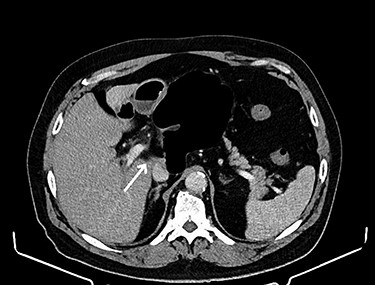

Reduction of the hernia could be challenging due to the marked distention of the entrapped intestinal loop (see Fig. 3). Bowel decompression through needle puncture or a small incision was frequently described to facilitate the reduction [7]. Another accepted option is widening the foramen of Winslow to aid reduction using Kocher’s maneuver [8]. The duodenum could be mobilized to the left by incising the peritoneum at its right edge. This technically demanding maneuver is reserved as a last resort. Bowel resection is indicated in case of a non-viable strangulated bowel. On the other hand, viable bowel is frequently reported, where no resection was needed [9]. Right hemicolectomy was described along with caecopexy and narrowing of the foramen Winslow as recurrence prevention maneuvers [7]. These maneuvers are highly debatable due to their added risk of postoperative morbidity in the lack of a hard evidence of recurrence, which remains more of theoretical risk [10].

Herniated caecum and ascending colon through the foramen of Winslow.